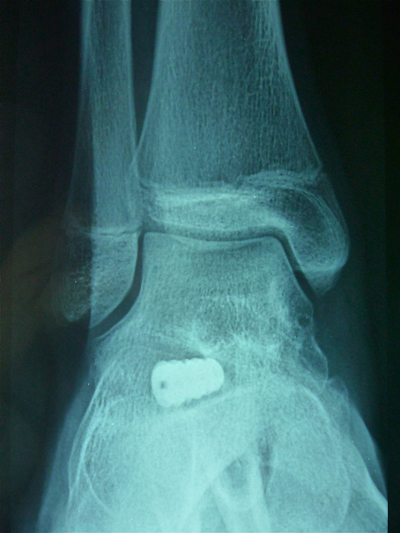

La radiographie de contrôle du pied droit: